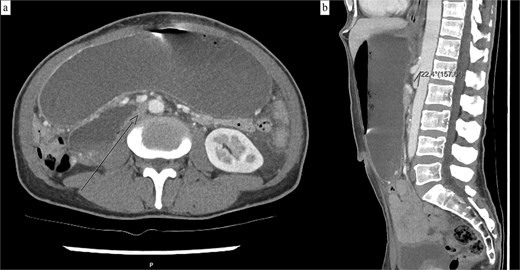

Progress CT showed interval improvement in gastric and small bowel dilatation, but persistent narrowing of the third duodenal segment beneath the SMA (Fig. 4). The patient tolerated reintroduction of oral feeding and was discharged after 2 days with no further nausea or vomiting. He remained well with no recurrence of obstructive symptoms four months later.

(a) Axial CT showing interval resolution of gastric dilatation with ongoing narrowing of the third duodenal segment between the aorta and SMA. (b) The aorto-mesenteric angle remains reduced at 22° on sagittal CT.